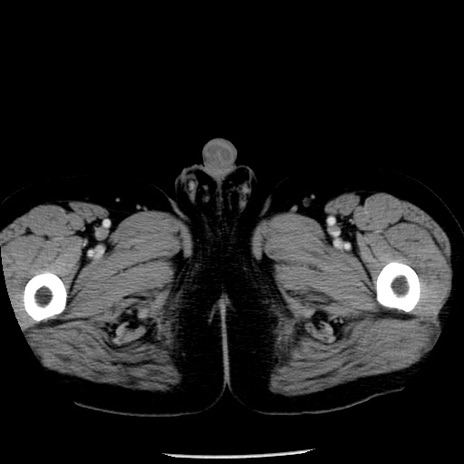

症例29(横断像)

【症例】40歳代男性

【現病歴】2日前から胃痛あり。徐々に周期的な激痛に変化した。本日になっても激痛があるため受診。

【身体所見】意識清明、BT 38-39℃台あり、腹部:膨満、やや硬、右下腹部に圧痛あり。

【データ】WBC 8500、CRP 23.26